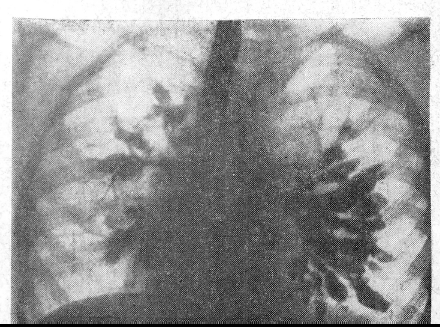

У Ш., 59 лет, при обычном рентгеновском исследовании отмечена зубчатость большой кривизны. Пальпаторно признаков нарушения эластичности выявить не удалось, и зубчатость была объяснена петлистостью утолщенных складок слизистой (рис. 1, см. вклейку). Однако у рентгенолога в оценке состояния большой кривизны возникли сомнения. Было решено вызвать больную для повторного просвечивания. В результате исследования, проведенного двуконтрастным методом, там, где обратила на себя внимание зубчатость большой кривизны, рисунок рельефа остался стабильным, в то время как во всех других отделах складки сгладились. Между обрывами плавных очертаний большой кривизны стенка желудка оказалась деформированной, ригидной (рис. 2). Заключение: раковая опухоль желудка. Больная госпитализирована. При гастроскопии на передней стенке и на большой кривизне желудка в нижней трети его тела выявлена плоская опухоль с четко очерченным валикообразным бугристым краем и изъязвлением в центре (рис. 3). При пробной лапаротомии найдена раковая опухоль 4X10 см, располагающаяся в области тела желудка. Имеются метастазы.

Рис.2. Двуконтрастная рентгенограмма той же больной, выполненная в положении лежа. Там, где была отмечена зубчатость большой кривизны, картина осталась стабильной. Между разрывами плавных очертаний большой кривизны стенка желудка деформирована, ригидна. Раковая опухоль желудка.